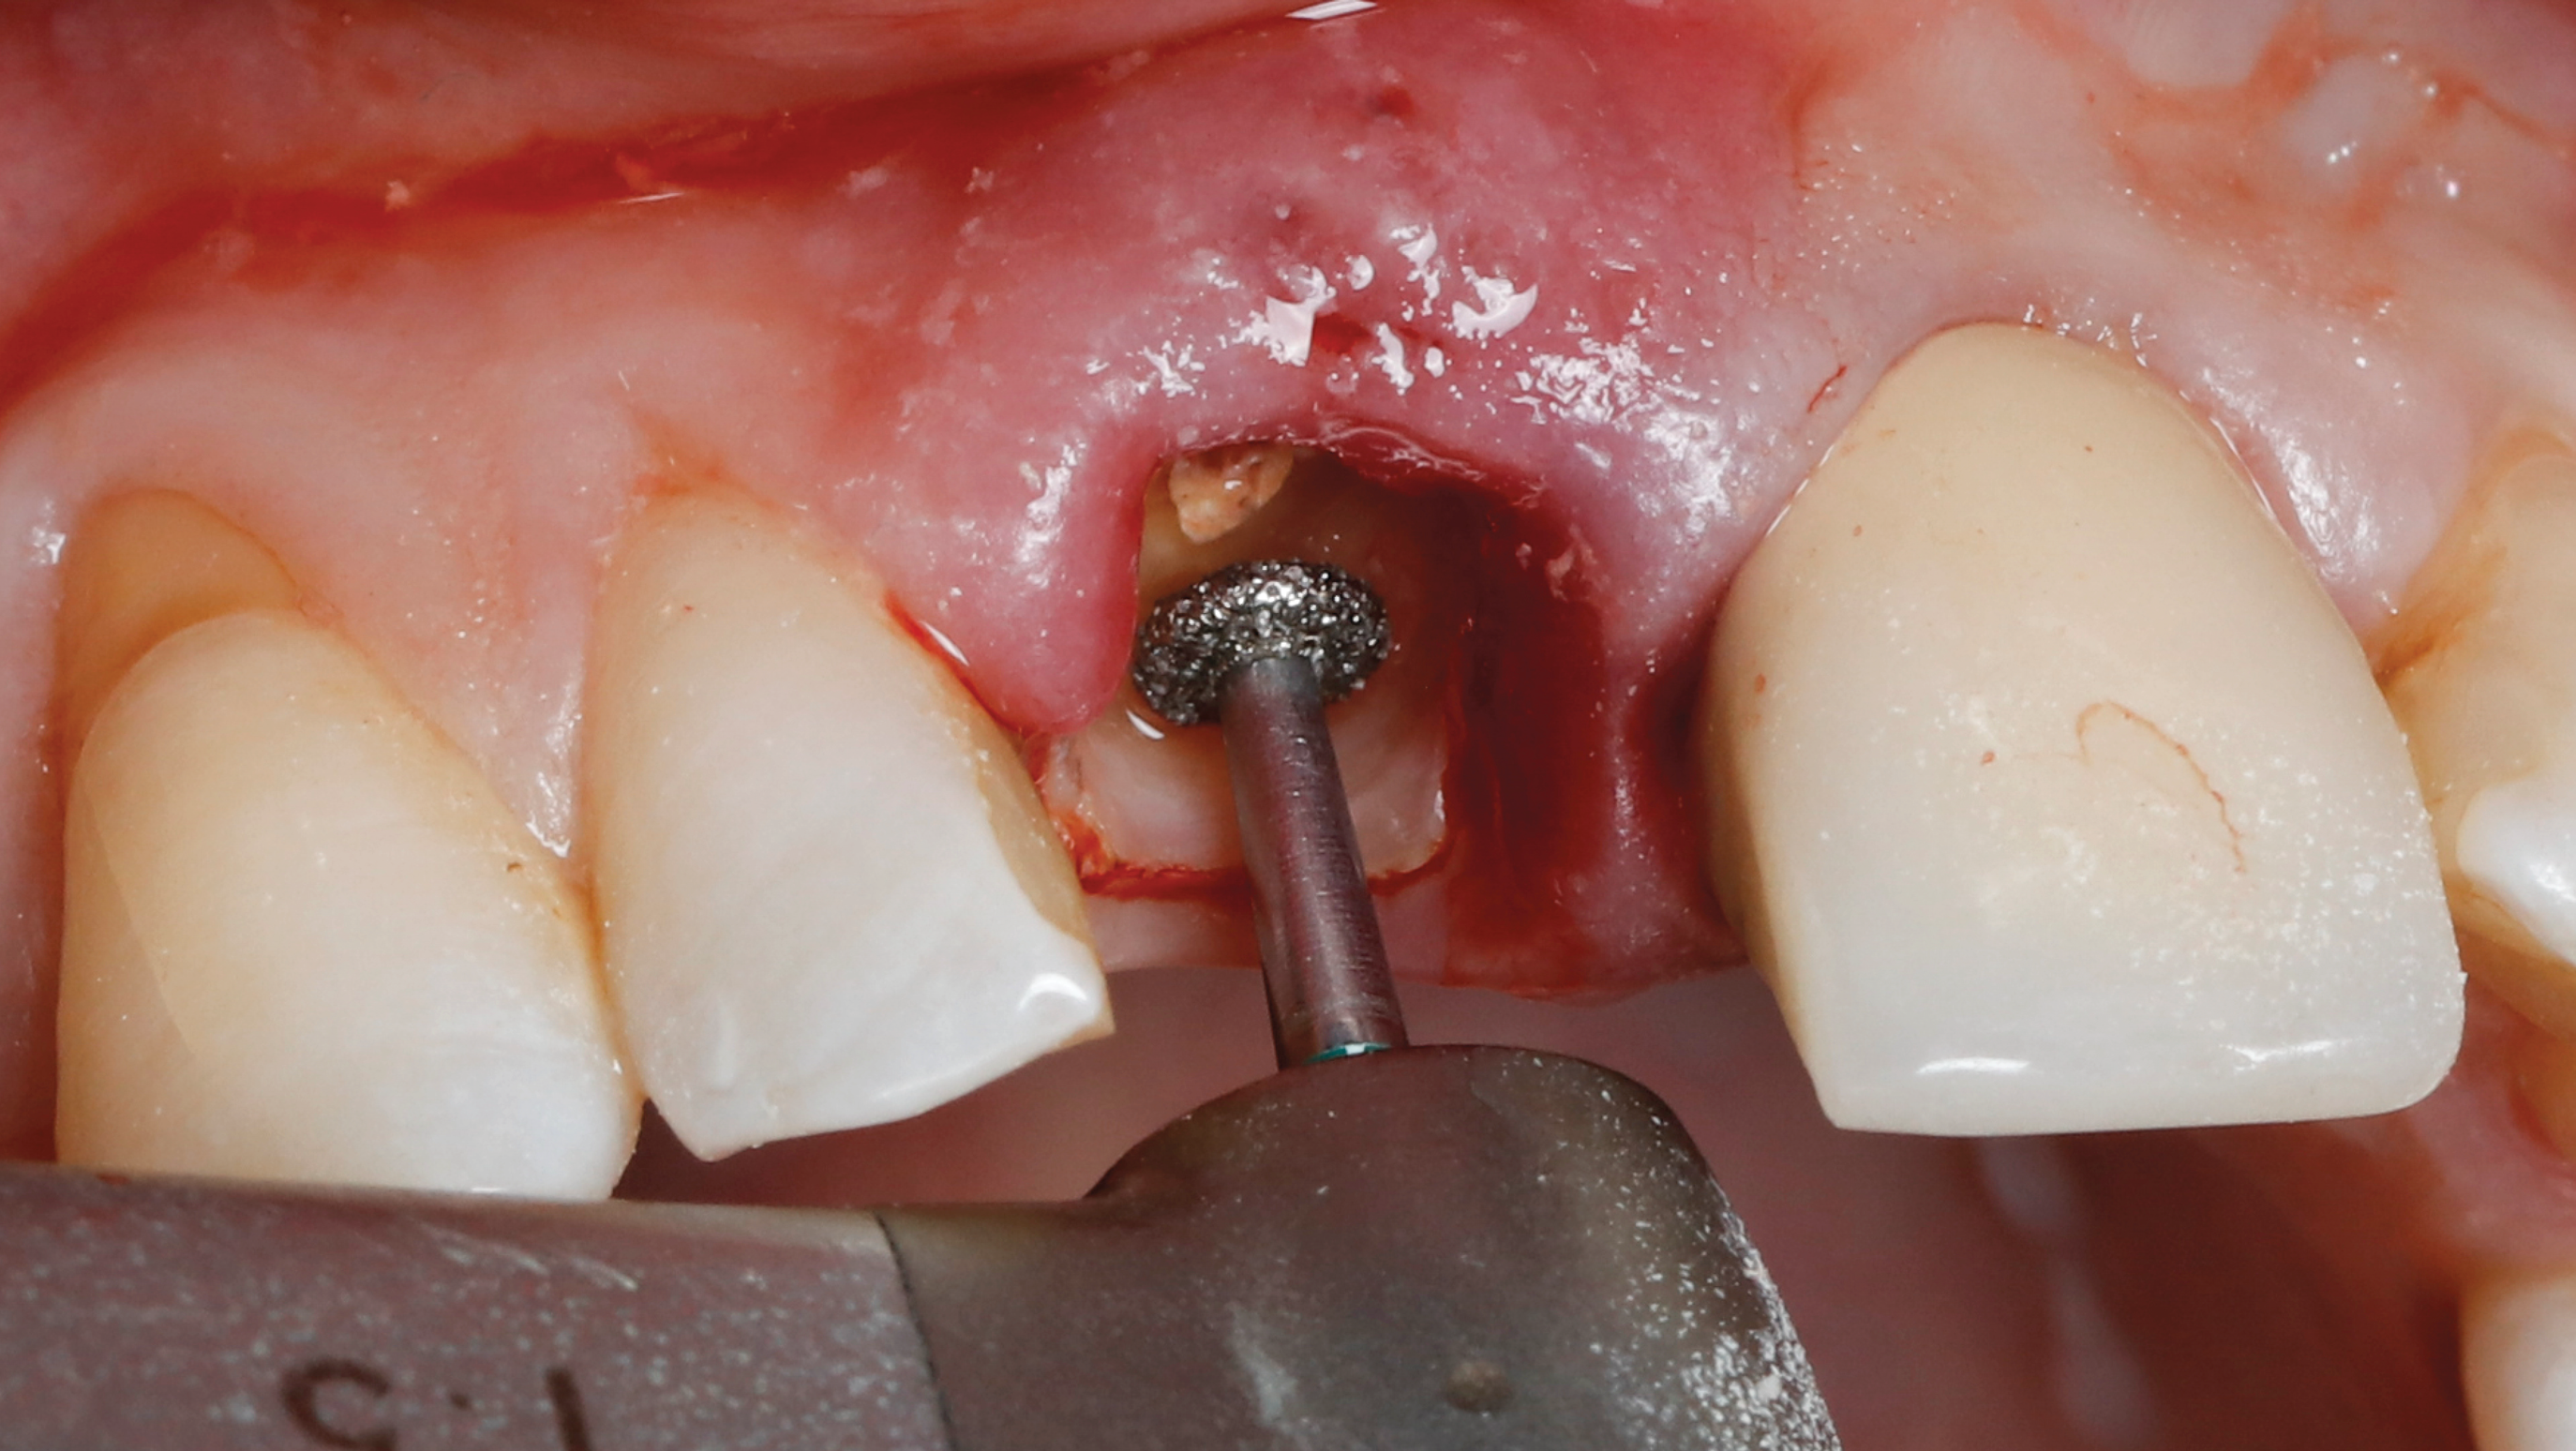

Fig 5. SPOT Step 1: After the clinical crown is removed, a high-speed diamond bur (Meisinger 801H-029) is used to hollow out the center of the tooth 2 mm to 3 mm subgingivally leaving a 1 mm rim of dentin around the root circumference.

Figure 5